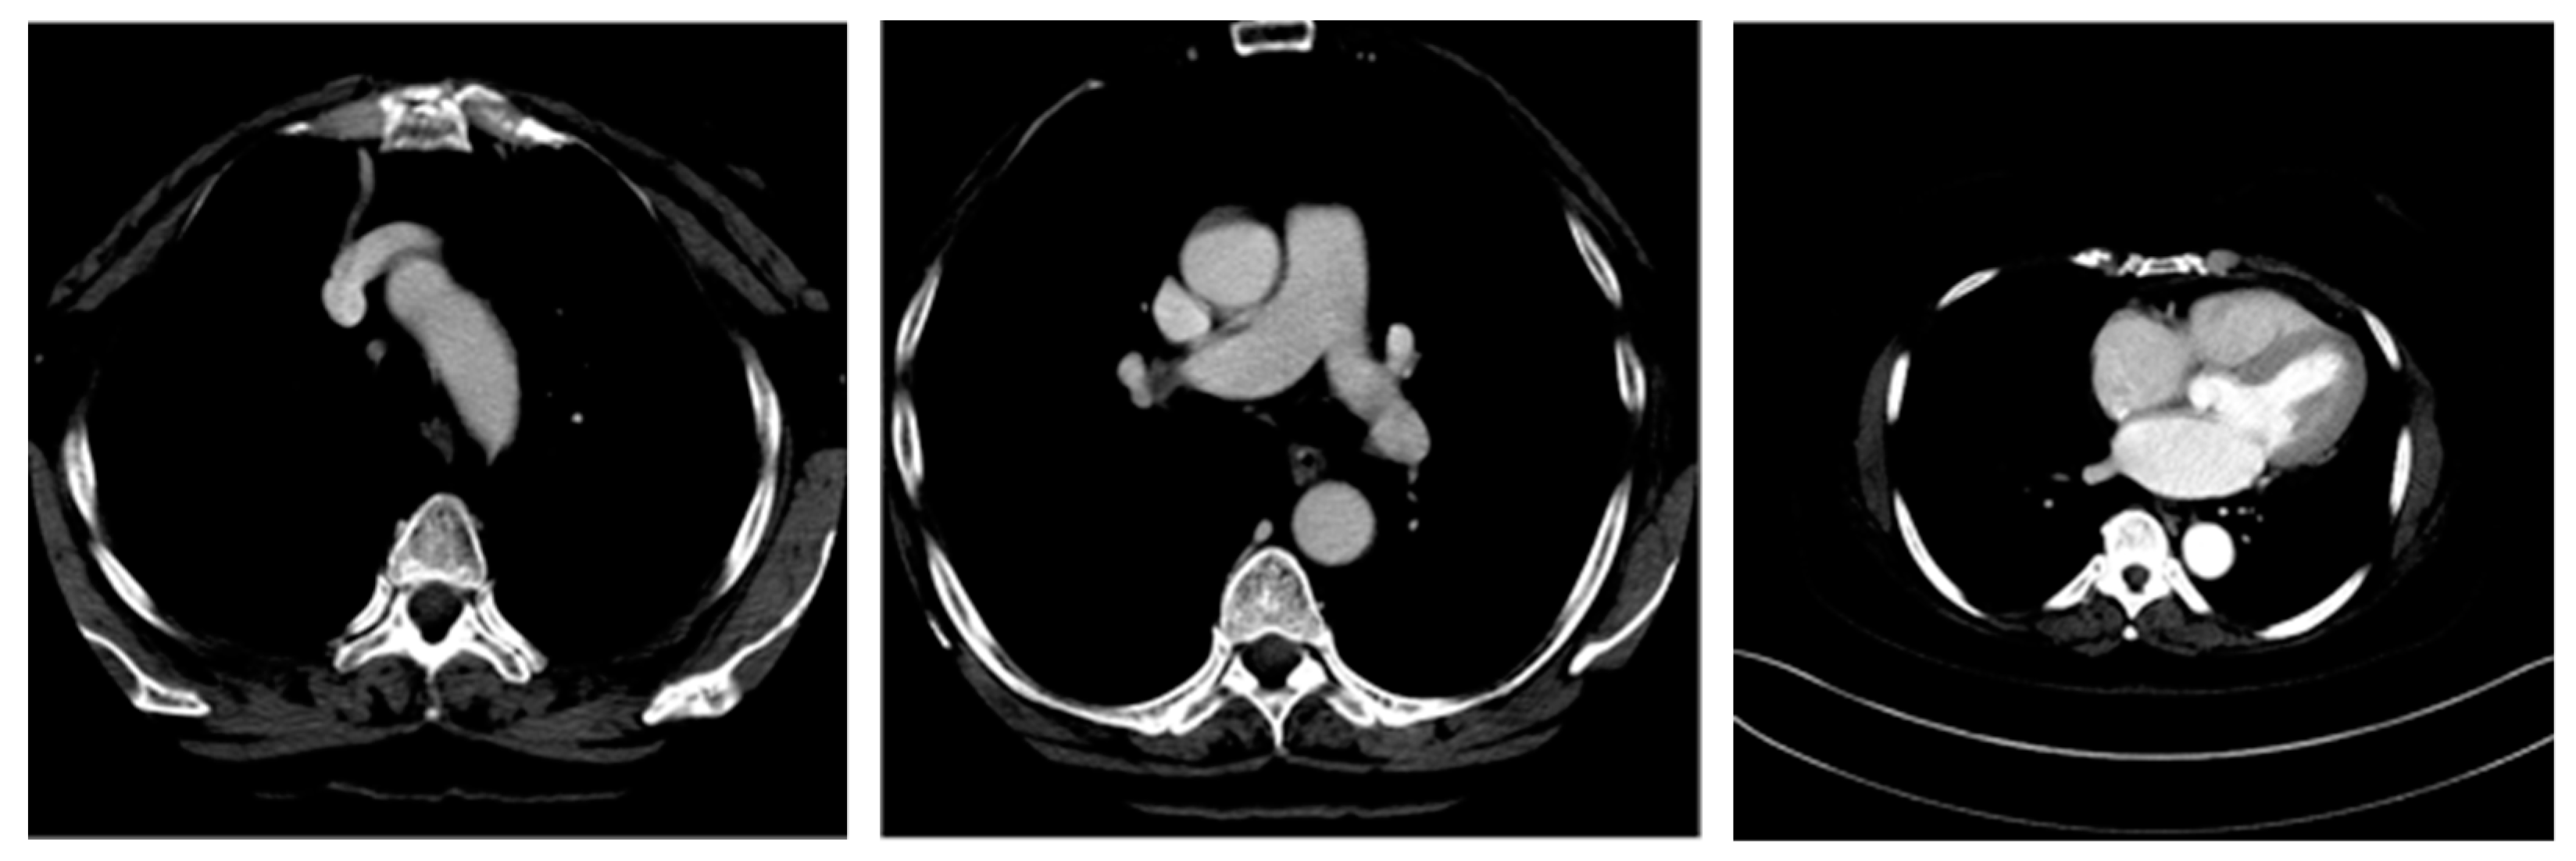

| Image Number | Overlaid Image | Deep Lesion Label | CNN Result | Clinical Radiologist’s Diagnosis | Grad-CAM Helpfulness |

|---|---|---|---|---|---|

| 1 | ![]() | Has Tumor | Has Tumor | Has Tumor | Some |

| 2 | ![]() | Has Tumor | Has Tumor | Has Tumor | Yes |

| 3 | ![]() | Has Tumor | Has Tumor | Has Tumor | Yes |

| 4 | ![]() | Has Tumor | Has Tumor | Has Tumor | Yes |

| 5 | ![]() | Has Tumor | Has Tumor | Has Tumor | Yes |

| 6 | ![]() | No Tumor | Has Tumor | Has Tumor | Yes |

| 7 | ![]() | Has Tumor | Has Tumor | Has Tumor | Yes |

| 8 | ![]() | Has Tumor | Has Tumor | Has Tumor | Yes |

| 9 | ![]() | Has Tumor | Has Tumor | Has Tumor | Some |

| 10 | ![]() | Has Tumor | Has Tumor | Has Tumor | Yes |